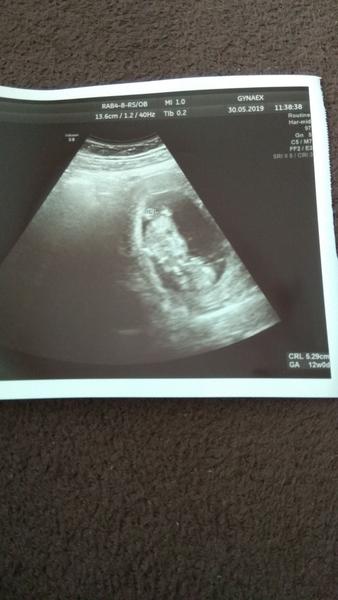

Ženy tak už mám tehu knižku 😍 aj NT ultrazvuk mám za sebou, všetko v poriadku, narástli sme👣. Krv výsledky mám v poriadku, dnes mi opäť brali krv. Minulý týždeň som bola na Nifty teste, tak budúci týždeň asi budem vedieť výsledok či je zdravé a ako bonus aj pohlavie. Konečne mám ukončený 12tt, padol mi kameň zo srdca dnes. Teším sa na vaše správy! krásne tehulkavanie 😘